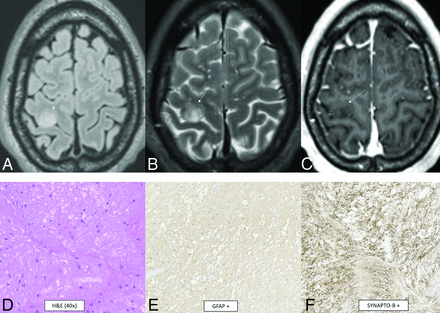

Myxoid glioneuronal tumor is a benign WHO grade 1 tumor that shows low-grade oligodendrocyte-like tumor cells with a myxoid-/mucin-rich stroma on histology. A fine capillary network is sometimes present along with neurocytic rosettes. Glial fibrillary acidic protein (GFAP) and OLIG2 are positive. The defining feature is a PDGFRA p.K385 mutation. Abnormalities in FGFR1, IDH1/2, BRAF, MYB, and MYBL1 are absent.36,37 Data are limited, but in the largest described series, the median patient age was 23.6 years (range, 6–65 years) with no sex predilection.38 These tumors have a propensity for the septum pellucidum.36,38 A typical mass is well-defined, lobulated, T1-hypointense, T2-hyperintense, nonenhancing, non-diffusion-restricting, and without surrounding edema. T2-FLAIR shows relative hypointensity centrally and hyperintensity peripherally (Fig 8). There is no elevated CBF. Larger lesions can appear L-shaped and have mass effect, which can mimic high-grade tumors.36⇓⇓-39

Myxoid glioneuronal tumor. MR imaging shows a mass in the right frontal horn region with peripheral T2-FLAIR hyperintensity and relative central T2-FLAIR hypointensity (A), which is slightly hypointense to CSF on the T2-weighted image (B), approaches the septum pellucidum (arrow, B), and does not enhance (C). There is no adjacent edema. Histology shows an oligodendroglioma-like appearance with moderate cellularity and uniform round nuclei with a circumferential arrangement around delicate vessels (D). Immunohistochemical staining is positive for OLIG2 (E), synaptophysin (F), and GFAP and negative for NeuN. This tumor has a PDGFRA p.K385 mutation and lacks FGFR1 abnormalities. Dysembryoplastic neuroepithelial tumor is a histologic mimic but has a mutation of FGFR1.